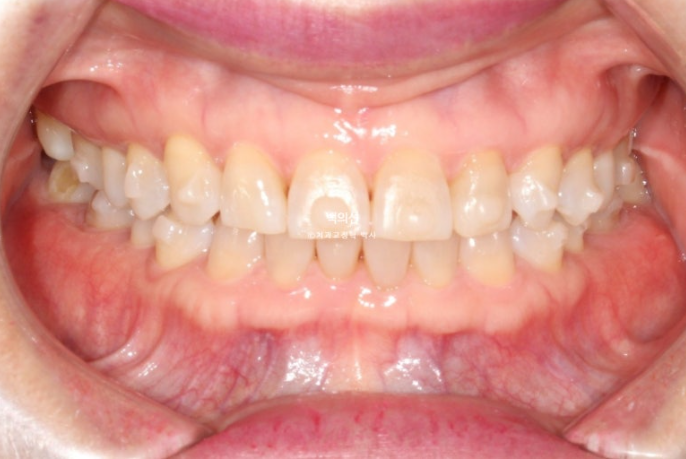

25.02

벌어진 틈을 메워놓는 레진을 제거한 모습입니다.

생각보다 틈이 꽤 크죠?

하지만 이 정도의 벌어짐, 틀어짐에는 인비절라인 익스프레스가 적절합니다.